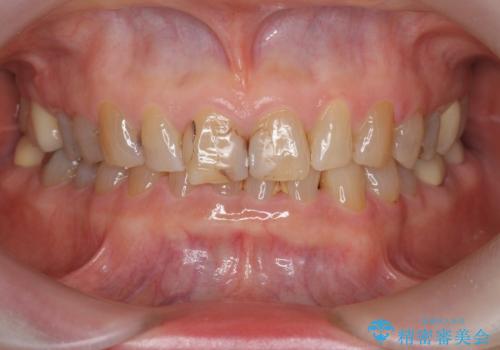

目立つ前歯の変色を改善したい

- 前歯の小さな虫歯を複数回治療した結果、つぎはぎだらけになってしまい審美的な改善を求めて来院されました。

これ以上のコンポジットレジン修復は更なる審美障害を招きかねないので、全体を覆うセラミッククラウンを選択します。

ディープバイト・噛み合わせが強いことからフルジルコニアクラウンを選択しました。